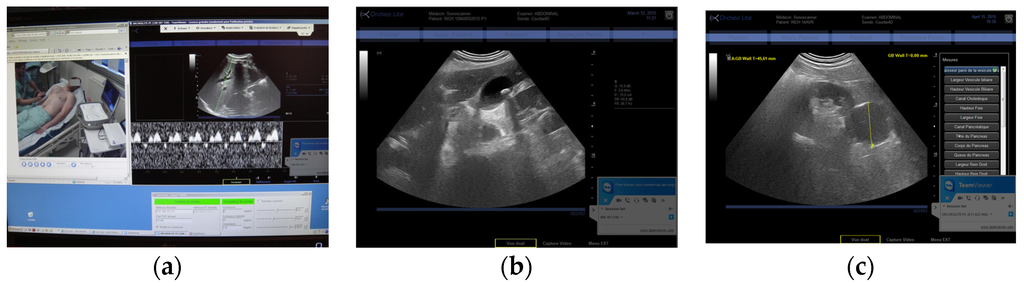

Figure 4. (a) Expert center computer screen for the MP with video of the patient (left), hepatic vein Doppler (right), and probe engine interface (bottom right); (b) View of gallbladder with lithiasis inside; (c) View of a renal cyst.

The three tele-echography methods used included: (a) a teleoperated robotic arm (RA) holding an ultrasound probe; (b) a teleoperated echograph with a motorized probe system (MP); and (c) remote guidance (RG). The RA (Figure 1) system consisted of a large structure that held a standard ultrasound probe. From the expert center (Figure 2), a trained sonographer performed the tele-echography examination by manipulating a dummy probe which teleoperated the robotic arm [1,3]. Throughout the examination, the non-sonographer operator at the patient site was required to position the robotic arm over the patient and to adjust the echograph functions and settings as directed by the trained sonographer. The second system of tele-echography, MP, consisted of a modified commercial echograph with motorized probes [2]. The ultrasound probes used for this system contained internal motors to tilt and rotate the probe transducer which the trained sonographer teleoperated from the expert center (Figure 3 and Figure 4). In addition to controlling the probe orientation, the echograph used for this system was modified to allow for the teleoperation of settings and functions. The final system of remote echography evaluated utilized RG (Figure 5) [5,6,7]. For this system, the non-sonographer (GP) had the probe in hand and performed the echographic examination as directed by a trained sonographer via videoconference.

A summary of the organs examined and the method used for each examination is presented in Table 1. Both the RA and the MP systems provided enough views of the deep organs of interest to deliver diagnoses in 97% of the cases (Figure 2 and Figure 4). For the superficial targets (organs and vessels), MP (Figure 4) and RG (Figure 5) provided the correct view of the organ necessary for the diagnosis in 98% of cases. Overall, tele-echography was not able to return enough information for a safe diagnosis in 11 of the 340 examinations (3.2%). These 11 cases involved imaging of deep organs (gall bladder, spleen, pancreas) on obese patients or patients with very poor echogenicity, and imaging of leg veins (femoral, tibial, gastrocnemius veins) on patients with substantial leg edema. For each of these cases, patients were referred to other medical centers for standard echography examinations.

Advancements in ultrasound probe technology lead to the recent development of the teleoperated motorized probe system. Much smaller and lighter than the RA (430 cm3, 400 g), the non-sonographer operators (GPs) found the MP system much easier to maneuver which resulted in shorter examination times. In addition, the low weight and general maneuverability of the motorized probes allowed for imaging along the side, and under the costal border of the patient, providing access to different acoustic windows without requiring the patient to change body position. As the MP system is limited by the availability of the specifically designed motorized probes, the probes constructed for the MP system were multi-frequency (3–5 MHz, and 5–15 MHz) to increase functionality. In contrast, the RA system could be modified to use a wide range of conventional ultrasound probes. However, due to its complex robotic technology, the RA system is much larger and more expensive than the MP system (50% higher cost). In the current study period, the medical professionals at the patient site and the trained sonographer did not have the option to choose between the RA and the MP systems as they were not available during the same time periods. However, after using each system for a minimum of six months, both medical professionals and patients expressed a preference for the MP method.